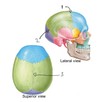

-bony case for the brain (hint: ‘neuro’) -8 bones -made of… 1.) calvaria (skull cap) - flat bones, frontal bone, parietal bone and occipital bone 2.) cranial base (floor, basicranium) - irregular bones with flat portions

What types of bones make up the skull cap? Specifically, what bones does the skull cap include?

flat bones parietal, occipital and frontal bones